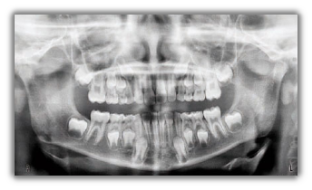

Gendex Orthoralix 8500 DDE vanta un design moderno che combina un’estrema funzionalità e semplicità d’uso con una gradevole estetica high-tech veramente accattivante, che non mancherà di valorizzare il vostro studio. Le immagini sono acquisite in modalità digitale mediante sensore CCD che la più recente ed avanzata tecnologia mette a disposizione. Il sistema dispone di quattro proiezioni: panoramica adulto, panoramica bambino, ATM frontale e ATM laterale.

Posizionato correttamente il paziente, Orthoralix 8500 DDE per mezzo della movimentazione multi-motorizzata dell’assieme monoblocco/sensore è in grado di generare sofisticate proiezioni specifiche per l’obiettivo diagnostico, producendo così immagini fedeli e nitide dell’intera regione dento-maxillo-facciale. L’ingrandimento si mantiene costante durante tutta l’esposizione garantendo immagini panoramiche caratterizzate da una minima distorsione radiografica.

Le immagini del nuovo Orthoralix 8500 DDE sono nitide e definite anche grazie alla piccola macchia focale del tubo radiogeno (solo 0,4 mm la più piccola nel settore). Utilizzando i più recenti algoritmi di elaborazione delle immagini digitali applicati ai dati che compongono la panoramica di questo sistema di nuova generazione, si ottengono radiografie che riproducono con precisione aree anatomiche critiche dei pazienti.